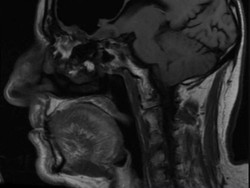

Penting! 60 Persen Risiko Stroke Bisa Dicegah, Begini Caranya

Stroke bisa disebabkan karena fiblirasi atrium (FA). Dengan deteksi dini FA, kita bisa mencegah terjadinya stroke, termasuk melakukan pemeriksaan rutin.